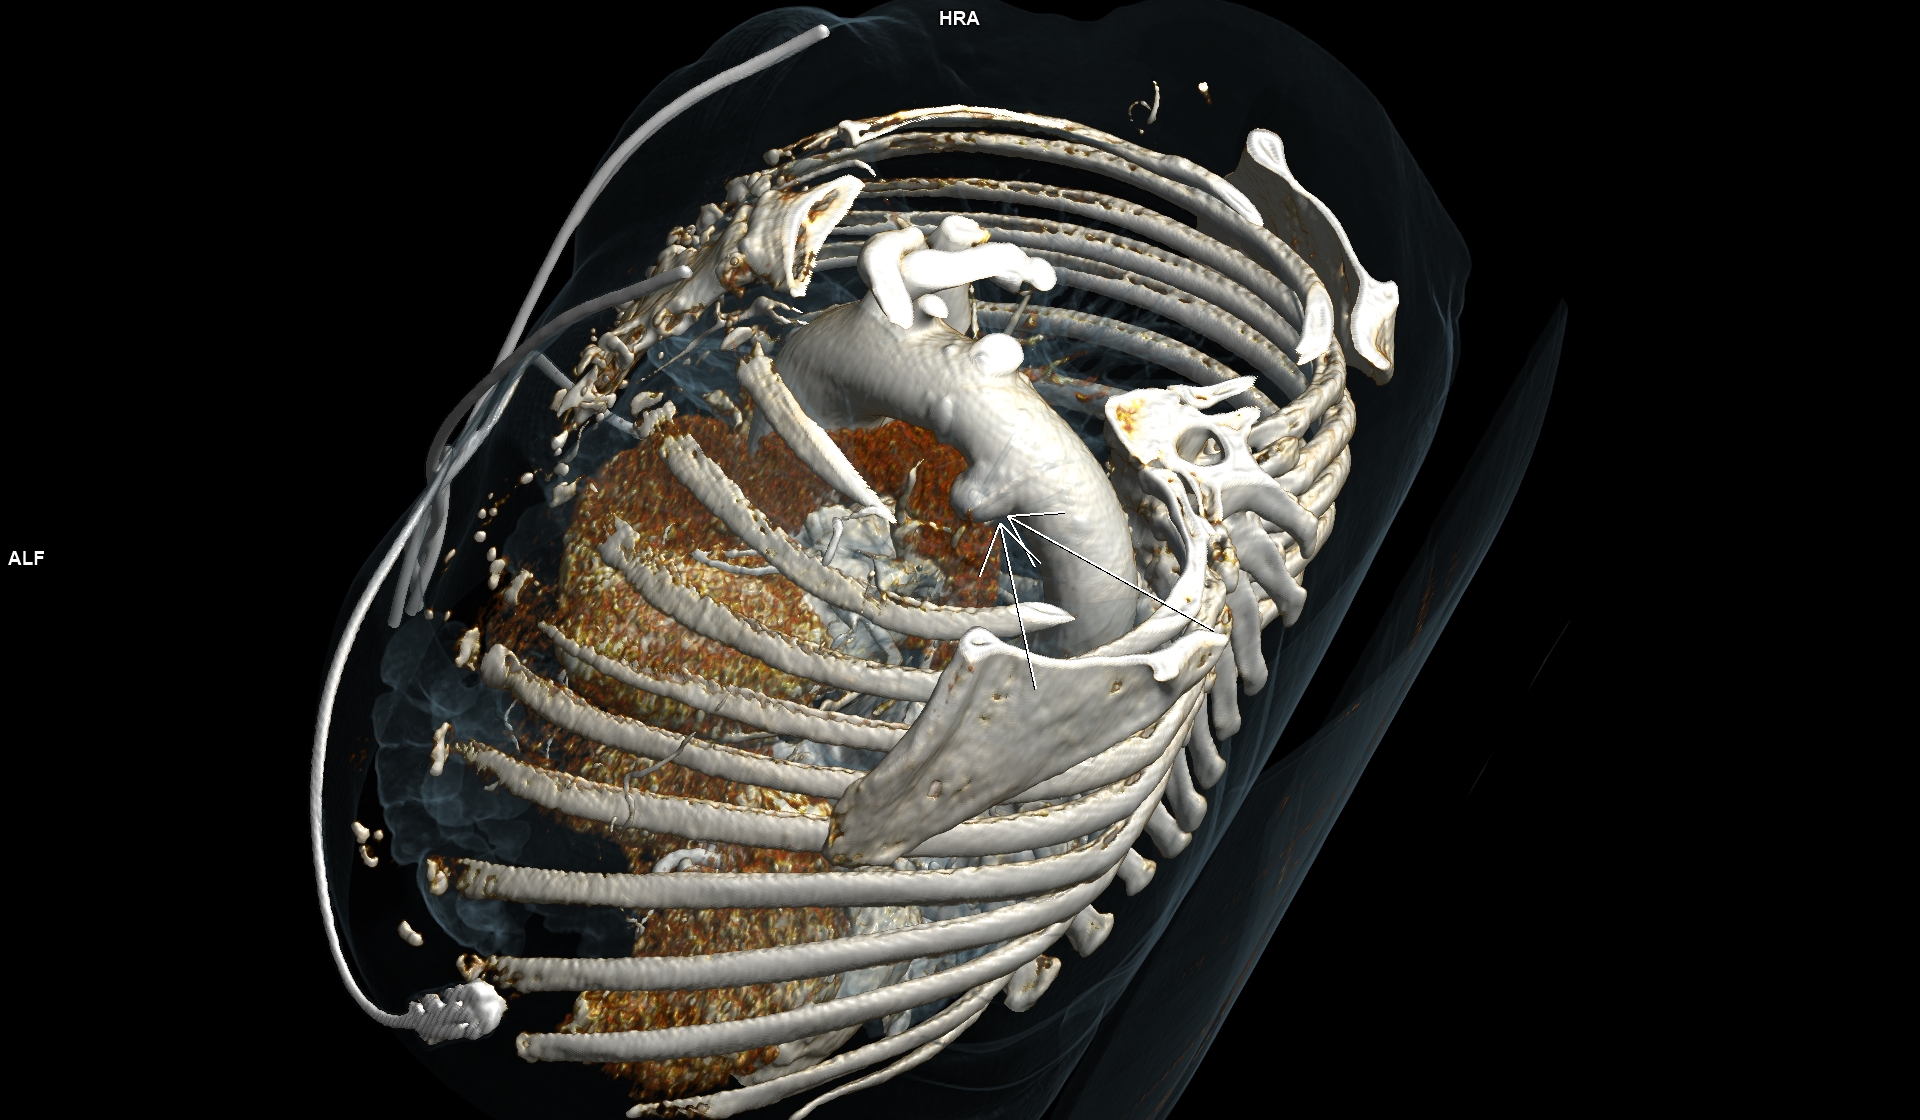

Figurile 3, 4, 5 si 6: reconstrucție volumică din achiziție angio în timp arterial – aorta toracică

Discuţie caz nr 102: Ductul arterial este o structura de by-pass între aorta descendentă și trunchiul de arteră pulmonară care funcționează în viață intrauterină deoarece plămânii nu sunt aerați; în mod normal se închide în primele zile după naștere. Imaginile prezentate arată că ductul arterial este închis însă se evidențiază creșterea calibrului unei reminiscențe a ductului arterial la deschiderea în aorta descendentă.

DE LUAT ACASĂ!!! Inserția ductului arterial în aorta descendentă toracică este util să fie cunoscută deoarece dacă avem canal arterial permeabil acesta poate fi de dimensiuni mici și poate să nu cauzeze probleme semnificative rămânând nedetectat – practic descoperire întâmplătoare.